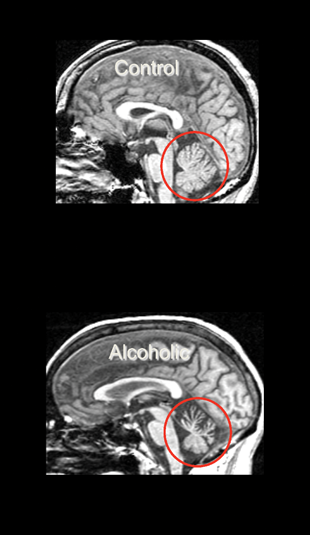

Alcoholic Cerebellar Degeneration (ACD)

ACD patients most frequently display ataxia, although other symptoms can include uncontrollable and repetitive eye movement (i.e., nystagmus) and speech problems resulting from impaired muscle control (i.e., dysarthria) (Fitzpatrick et al. 2012). Neuroimaging in ACD demonstrates damage disproportionately apparent in anterior superior portions of the cerebellar vermis (Sullivan et al. 2000a), with postmortem pathology indicating loss of cerebellar Purkinje cells (Feuerlein 1977).

CPM targets the pons and ACD affects the cerebellum. Total infratentorial volume (including pons, cerebellar hemispheres, vermis, fissures, cisterns, and fourth ventricle) is significantly smaller in uncomplicated alcoholics than control subjects. The volume of the pons (Chanraud et al. 2009b; Pfefferbaum et al. 2002b; Sullivan 2003) and cerebellum (i.e., hemispheres) (Boutte et al. 2012; Chanraud et al. 2007, 2009a; De Bellis et al. 2005; Sullivan et al. 2000a,c) is smaller in uncomplicated alcoholics than in normal controls. Alcoholism-related volume deficits are also prevalent in gray and white matter (Shear et al. 1996; Sullivan et al. 2003) of the cerebellar vermis (Antunez et al. 1998; Piguet et al. 2006; Sullivan et al. 2006b, 2010), predominately in anterior superior but not posterior inferior regions (Sullivan et al. 2000a) (see figure 6).